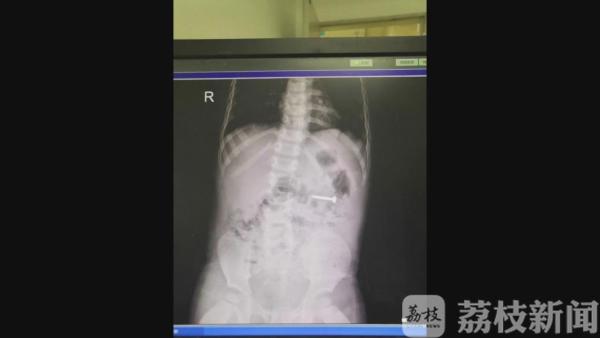

送医之后,通过CT检查发现,这颗钉子就位于患儿的十二指肠区域,约3厘米,头端尖锐,钉体有螺纹。自行排出体外可能性很小。